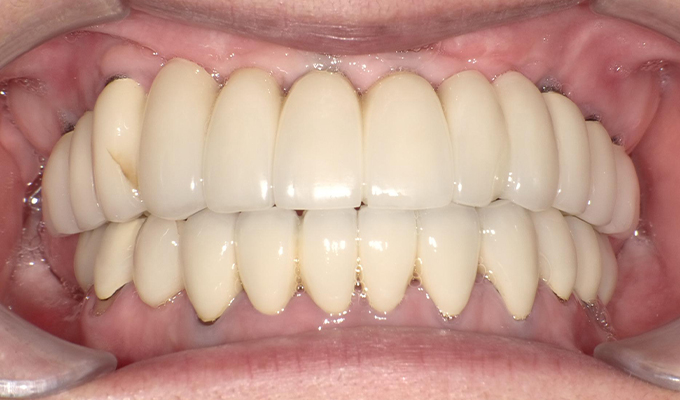

case1インプラントとメタルボンドブリッジの症例

初診時(2010年)

初回メンテナンス時(2014年)

最新メンテナンス時(2024年)

- 初診時の年齢

- 60代女性(2010年)

- 主訴

- ちゃんと咬めるようになりたい。最近孫が生まれたから一緒に歌ったりしたいけど、今は歌うこともできないから・・・・。と

- 治療内容

- 5年ほど前に入れ歯を作ったそうですが合わなかったので使用してなかったせいか前歯がグラグラになっていて今にも抜けそうな状態でした。

保存が難しい歯を抜歯し、上はインプラント8本、下は奥歯にインプラント4本埋入しました。

補綴は変色しないメタルボンドを選択されたので治療完了して11年経過してもとてもきれいな状態で維持されています。

初診時にお話しされていたお孫さんも中学2年生になったそうで、歯の治療をしたおかげで充実した毎日が送れてます、とメンテナンス時もいつも嬉しそうにされています。